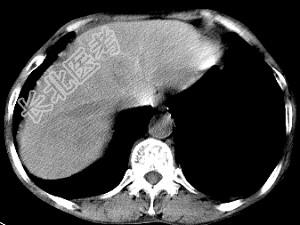

- 单项选择题男,40岁有血吸虫感染史, 腹胀不适,食欲减退, CT扫描所见如图,最可能诊断为 ( )

A、脂肪肝

B、肝炎后肝硬化

C、血吸虫后肝硬化

D、酒精性肝硬化

E、胆汁性肝硬化